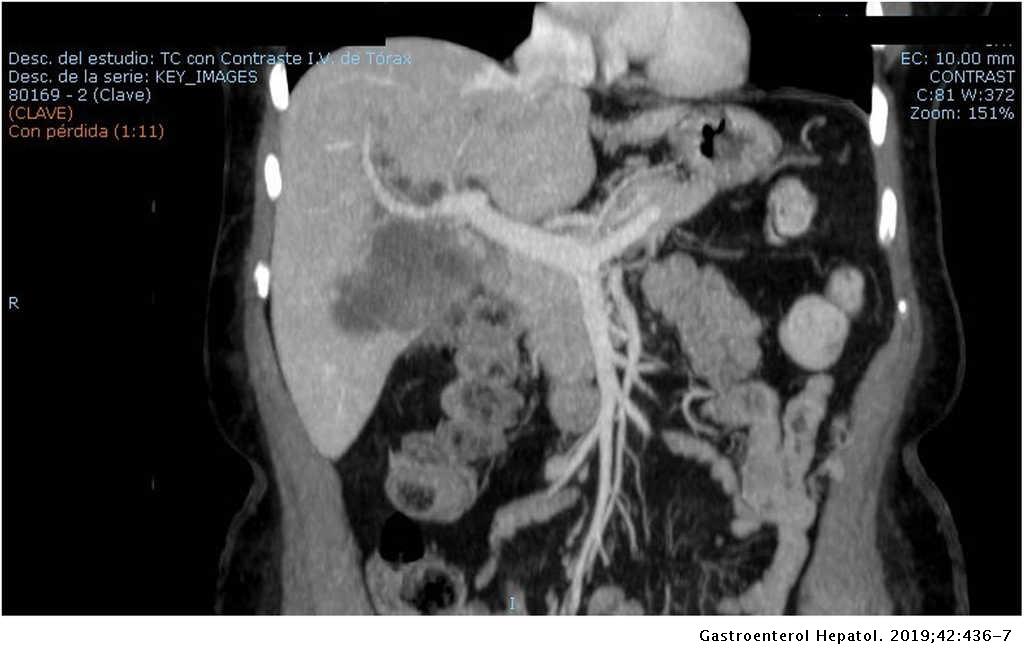

Colangiocarcinoma

Cholangiocarcinoma CT wikidoc

Stadiazione prechirurgica, in paziente con colangiocarcinoma

Manejo y diagnóstico del colangiocarcinoma formador de masa a propósito